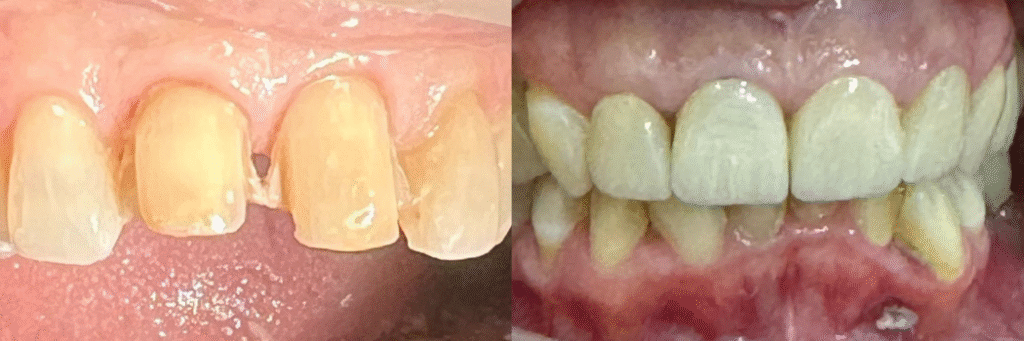

Múltiples carillas en estética desfavorable

A small river named Duden flows by their place and supplies it with the necessary regelialia. It is a paradisematic country, in which roasted parts of sentences fly into your mouth. Even the all-powerful Pointing has no control about the blind texts it is an almost orthographic life

One day however a small line of blind text by the name of Lorem Ipsum decided to leave for the far World of Grammar. The Big Oxmox advised her not to do so, because